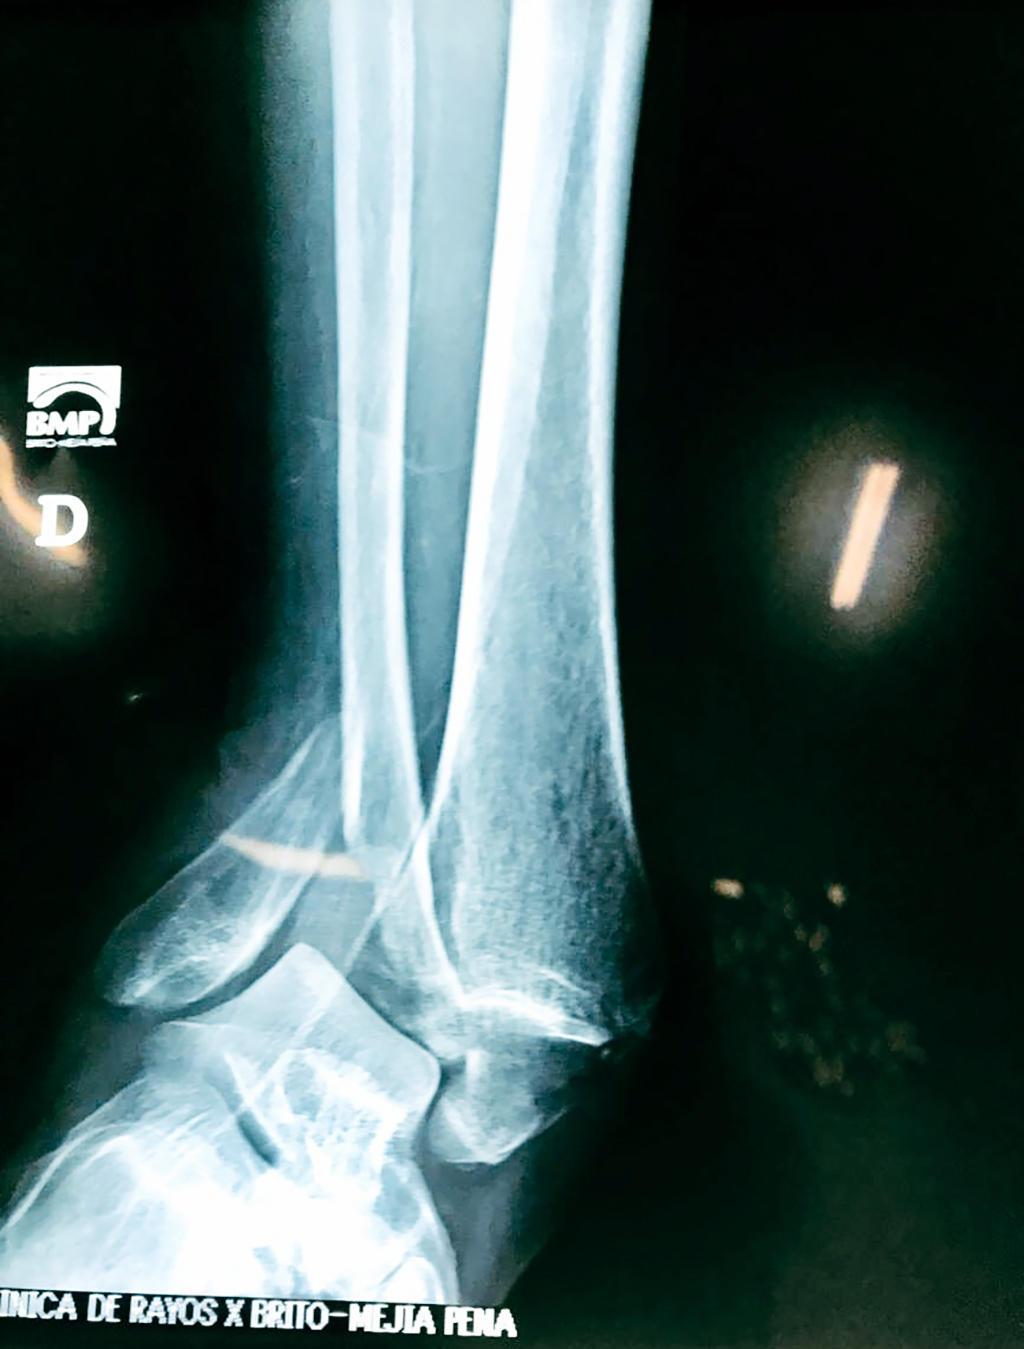

Algunas fracturas de tobillo pueden requerir cirugía si:

- Los extremos de los huesos están desalineados entre sí (desplazados).

- La fractura se extiende hasta la articulación del tobillo (fractura intra-articular).

- Los tendones o ligamentos (tejidos que sujetan los músculos y los huesos entre sí) están rotos.